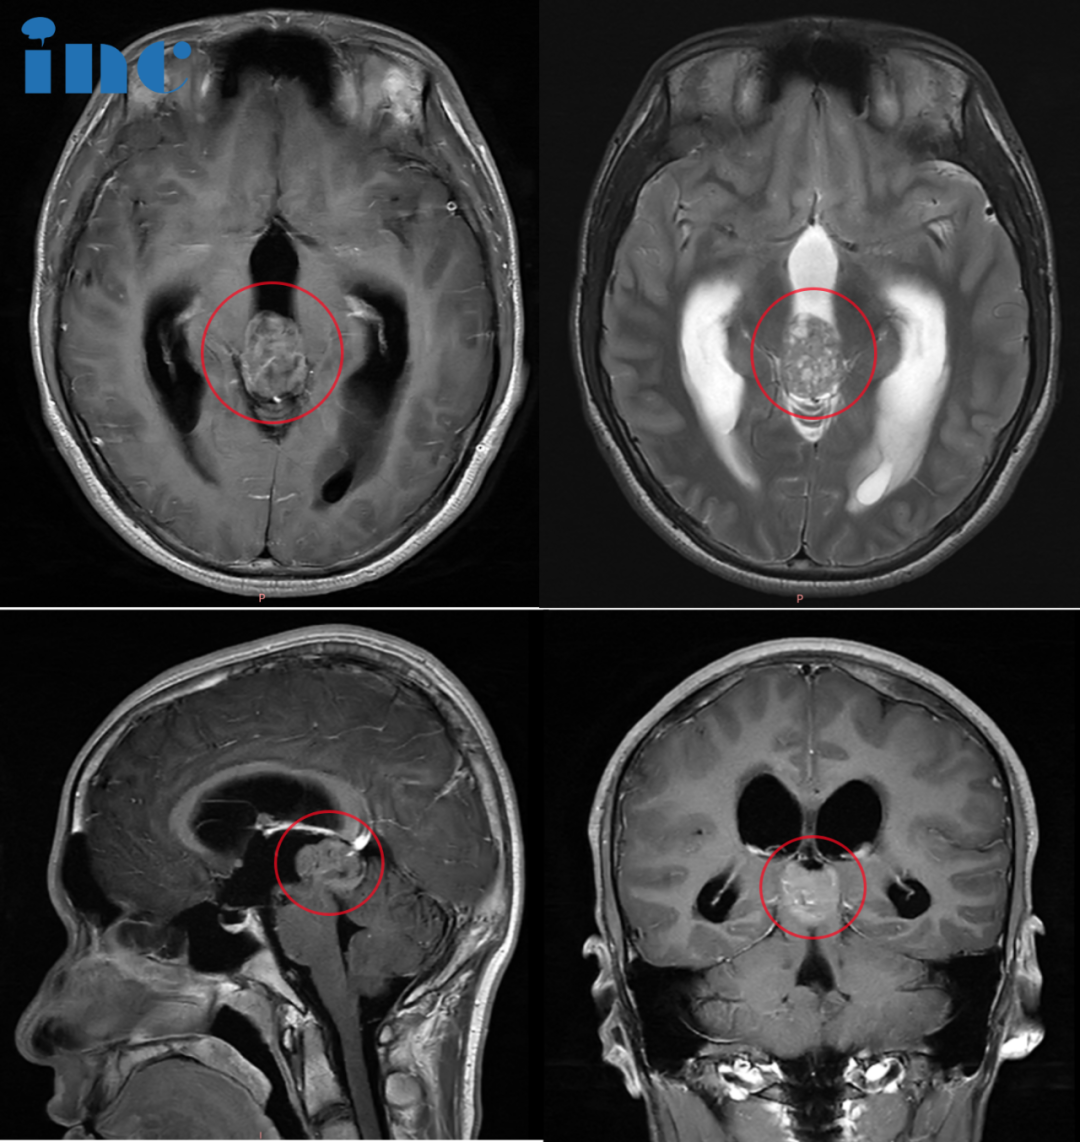

.1. 与瘤共存6年 希望越大,失望越大 10岁,林林被查出一个位于松果体区的钙化病变。由于位置特殊,体积较小,医生均建议保守观察。钙化,意味着肿瘤生长缓慢,林林一家放下心来,希望在...